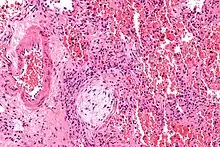

| Micrograph showing a Masson body (off center left/bottom of the image – pale circular and paucicellular), as may be seen in cryptogenic organizing pneumonia. The Masson body plugs the airway. The artery associated with the obliterated airway is also seen (far left of the image). H&E stain. | |

Organizing pneumonia is usually preceded by some type of lung injury that causes a localized denudation or disruption in continuity of the epithelial basal laminae of the type 1 alveolar pneumocytes that line the alveoli.[9] This injury to the epithelial basal lamina results in inflammatory cells and plasma proteins leaking into the alveolar space and forming fibrin, resulting in an initial fibroblast driven intra-alveolar fibroproliferation.[9] The fibroblasts differentiate into myofibroblasts and continue to form fibrosis resulting in intra-alveolar fibroinflammatory buds (Masson's Bodies) that are characteristic of organizing pneumonia.[9] These Masson's bodies consist of inflammatory cells contained in an extracellular matrix consisting of type I collagen, fibronectin, procollagen type III, tenascin C and proteoglycans.[9] Angiogenesis , or the formation of blood vessels, occurs in the Masson's bodies and this is driven by vascular endothelial growth factor.[9] Remodeling occurs, resulting in the intra-alveolar fibroinflammatory buds (Masson's Bodies) moving into the interstitial space and forming collagen globules that are then covered by type 1 alveolar epithelial cells with well developed basement membranes. These type 1 alveolar epithelial cells (pneumocytes) then proliferate, restoring the continuity and function of the alveolar unit.[9] This process is in contrast to the histopathologic changes seen in usual interstitial pneumonia where extensive fibrosis and inflammation occur leading to fibroblastic foci to form in the alveolar spaces resulting in obliteration of the alveolar space, scarring and significant damage to lung architecture (the alveoli).[9]

Biopsy findings in patients with organizing pneumonia consist of loose connective tissue plugs involving the alveoli, alveolar ducts and bronchioles. The loose connective tissue plugs occupying the alveolar spaces often connect to other connective tissue plugs in nearby alveoli via the pores of Kohn creating a characteristic butterfly pattern on histology.[9] There is usually minimal to no interstitial inflammatory changes in biopsies of organizing pneumonia.[9]

Histologically, cryptogenic organizing pneumonia is characterized by the presence of polypoid plugs of loose organizing connective tissue (Masson bodies) within alveolar ducts, alveoli, and bronchioles.